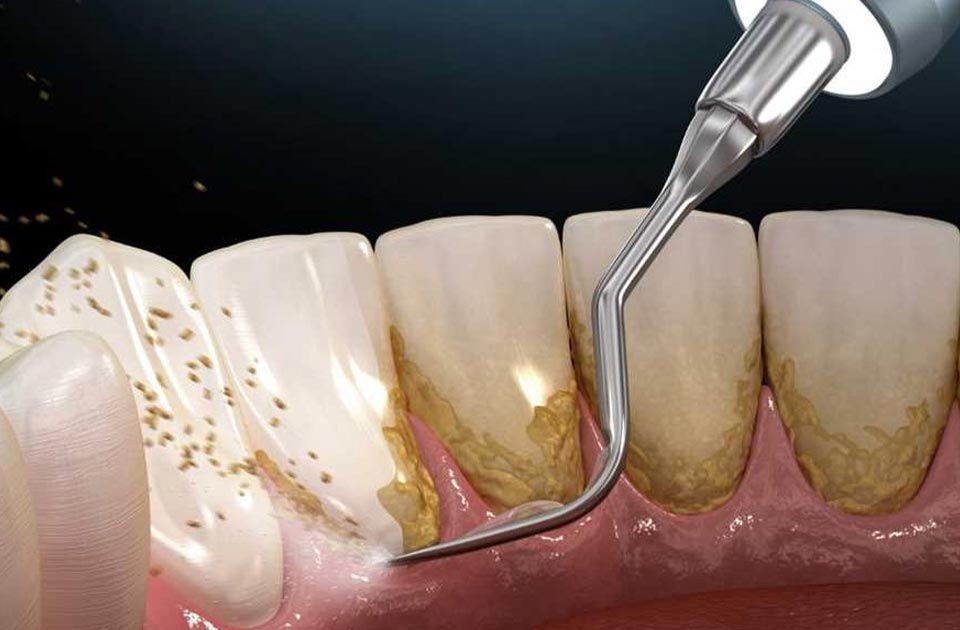

امروزه بسیاری از کلینیک های دندانپزشکی خدمات جرم گیری دندان را به مراجعه کنندگان خود ارائه می دهند اما بیماران زمانی که برای درمان جرم گیری دندان به یک کلینیک دندانپزشکی مراجعه می کنند نا خودآگاه چند سوال را با خود تکرار می کنند که یکی از این سوال ها این است که آیا جرم گیری دندان درد دارد ؟ یا جرم گیری دندان باعث آسیب به دندان من می شود ؟

شاید شما هم ار افرادی باشید که به بهداشت دهان و دندان خود اهمیت زیادی می دهید و می خواهید برای جرم گیری دندان های خود اقداماتی را انجام دهید جرم گیری دندان یکی از خدمات پر طرفدار و مهم یک کلینیک دندانپزشکی می باشد که از اهمیت زیادی برخوردار هست .

ممکن است که بعد از انجام جرم گیری دندان فرد دچار احساس ناراحتی شود که در این حالت دندان های فرد حساس هستند و به دمای سرد و گرم حساسیت نشان می دهد و یا ممکن است که لثه ها متورم شوند که طبیعیست و بعد از چند روز این علائم از بین می روند .

می توان گفت که خدمات جرم گیری دندان دردی ندارد با این حال ممکن است که ناراحتی هایی موقتی را به وجود بیاورد که می توان خوردن مسکن ها مانند نوافن ، ایبوپروفن یا استامینوفن این درد ها را کنترل کرد .

پس در نتیجه خود خدمات جرم گیری دندان دردی را ندارند و فقط ممکن است ناراحتی های موقتی را داشته باشد که با مصرف مسکن ها قابل کنترل کردن می باشد .